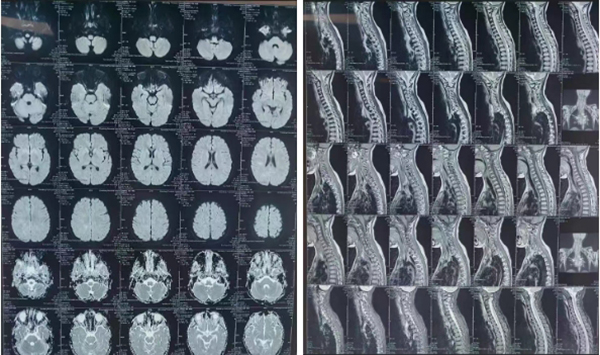

入院时,欣欣呈昏迷状态,高热,在无创呼吸机辅助呼吸下仍有呼吸困难,经皮氧饱和度仅为88%,四肢肌力均0级,腱反射消失。小儿重症医学科负责人靳有鹏教授带领团队对欣欣的病情进行了全面评估,先给予气管插管、呼吸机辅助呼吸,并积极完善相关辅助检查。颅脑及脊髓MR检查提示:双侧侧脑室周围、放射冠、基底节区、脑干及皮层下见多发斑点状、斑片状异常信号,脊髓全长肿胀。呼吸道病原学检测发现腺病毒阳性。经与小儿神经科会诊讨论后,明确诊断为急性播散性脑脊髓炎合并腺病毒及耐药支原体感染、呼吸衰竭。神经系统损伤累及范围很广,包括脑内大片区域及全脊髓,同时欣欣还存在腺病毒及耐药支原体感染。单纯腺病毒感染病死率极高,合并耐药支原体感染后,治疗难度极大,预后极其不乐观。

患儿入院时的颅脑和脊髓MR